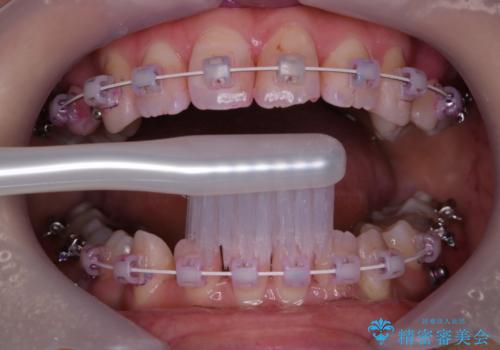

- ワイヤー矯正中のメンテナンスでPMTCを希望されました。染め出しを行い、歯ブラシ指導とPMTC30分コースを行いました。

毎日しっかりと磨いているようでも、装置の周りや歯と歯の間・歯と歯茎の間に磨き残しが残ってしまいます。そのため磨き残しをチェックする『染め出し剤』を使用すると明確に磨き残しを見ることができます。

この部分をしっかりと磨けるようになると、虫歯や歯周病を予防することができます。

矯正中にも、虫歯や歯周病予防をしっかり行うことが大切です。